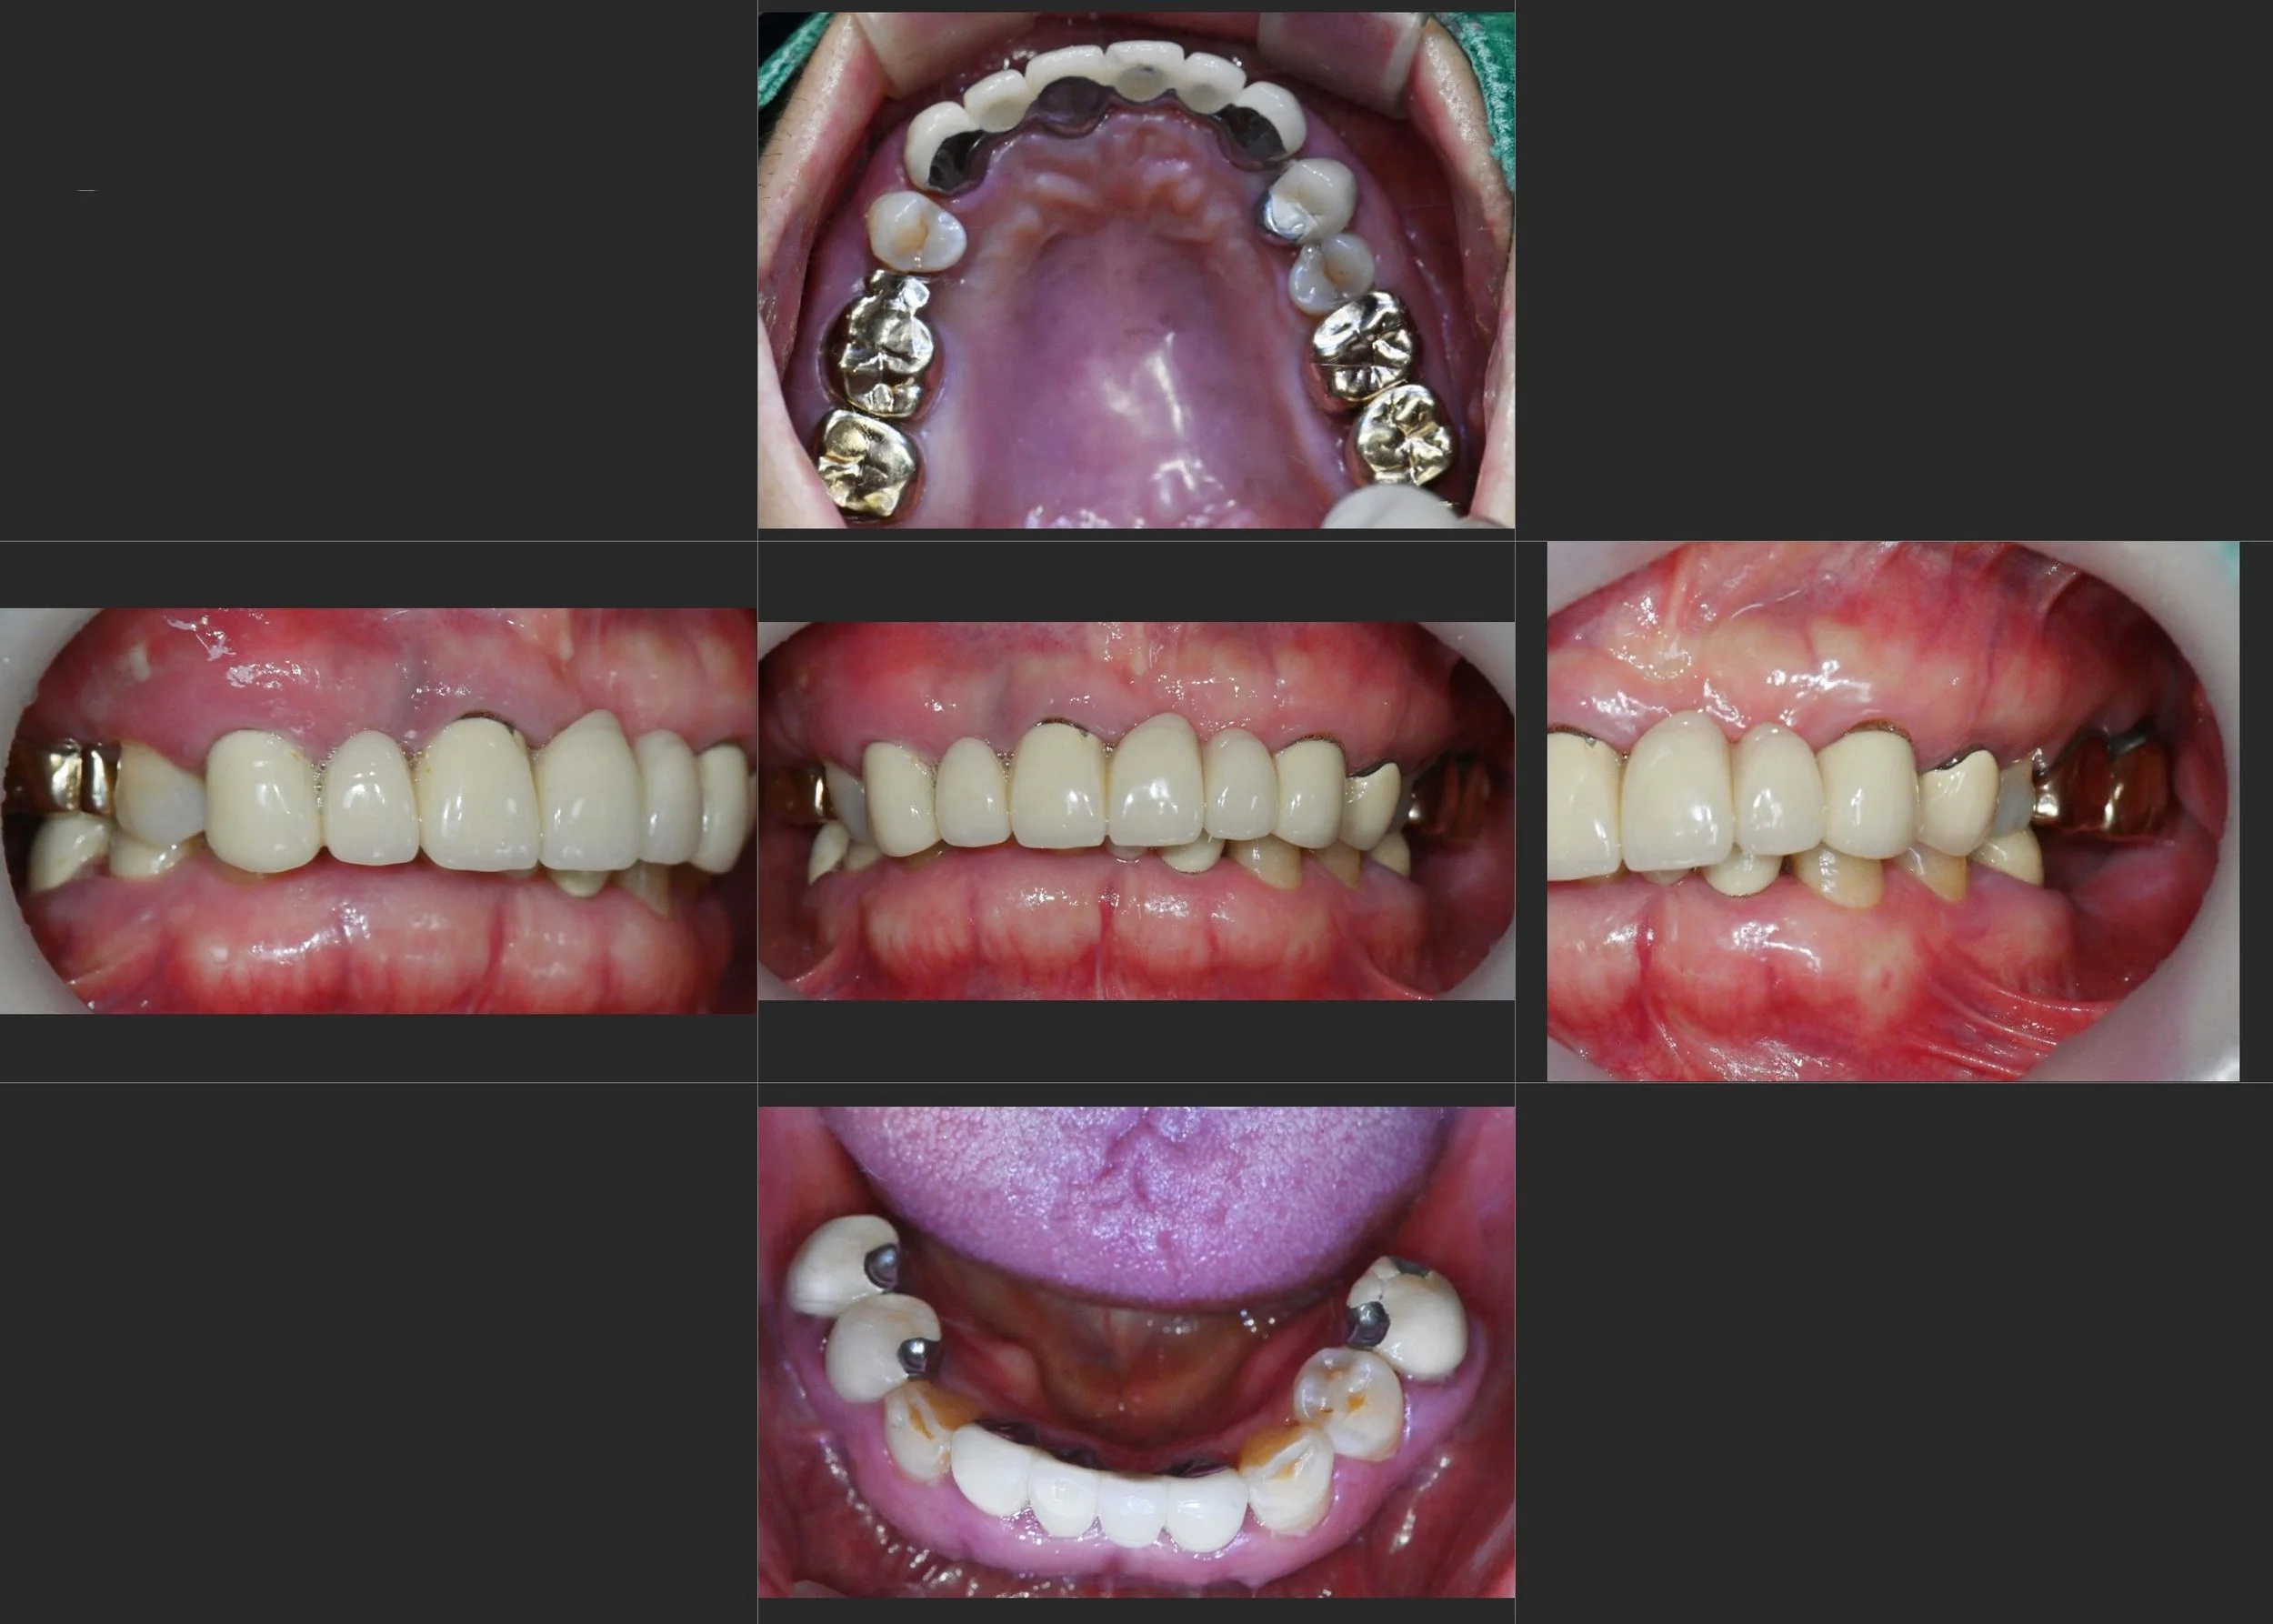

INTRA ORAL - BEFORE

INTRA ORAL - AFTER

Despite functional impairment, the patient wished to avoid anterior re-prosthetic

treatment due to financial considerations.

• Functional rehabilitation prioritised over anterior aesthetic refinement